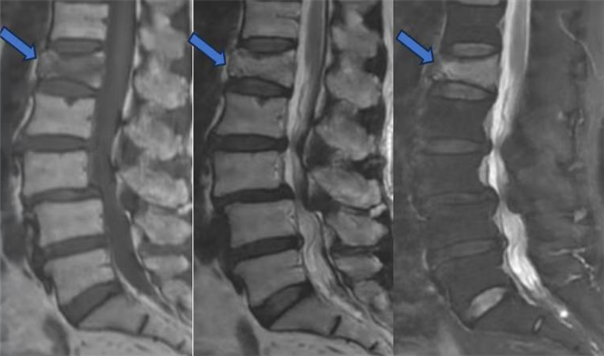

1、DR,CT,MRI均可用于骨质疏松性骨折的诊断,直观显示骨折区域。

MRI